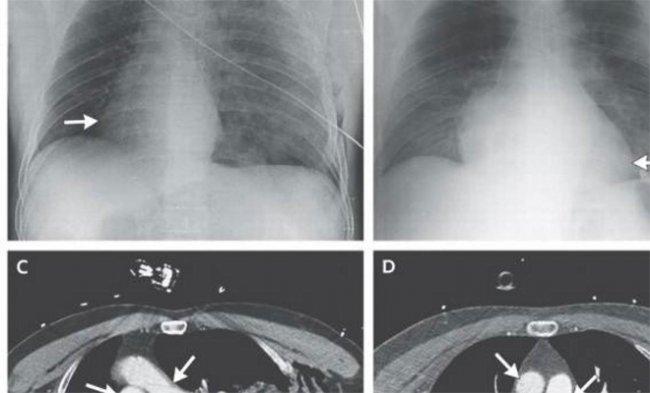

Сердце, повернувшееся на 900

Это произошло в Италии в 2014-ом. После аварии у поступившего в приемный покой больницы мотоциклиста проявилось ненормальное "поведение" сердца. Его ритм был замедлен, отмечались перебои. После обследования доктора выявили поворот сердца вправо под прямым углом. Такое положение - декстрокардия, считается врожденным дефектом. Поворот вследствие аварии наблюдался впервые в медицинской практике. На счастье парня, врачи смогли повернуть вспять нежелательное изменение положения сердца.